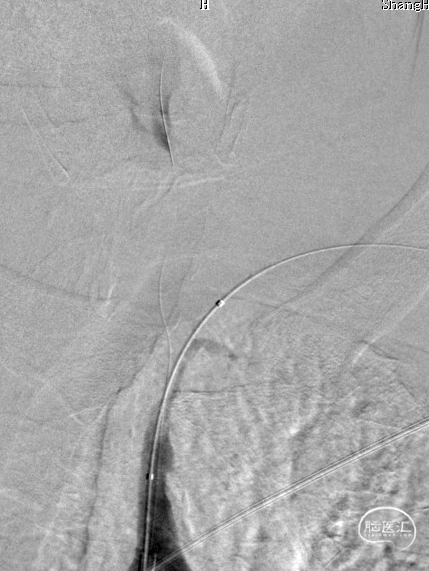

0.018*300cm 外周导丝至左肱动脉,0.014*200cm 通桥北斗SS™神经血管导丝超选至左椎V2段远端。

沿0.018*300cm 外周导丝送入6*40 外周球囊送至左侧锁骨下动脉狭窄处,压力泵逐渐加压到6atm。

撤出球囊后见残余狭窄40%。

再次沿0.018*300cm 外周导丝送入6*40 外周球囊达LSub狭窄部位,压力泵逐渐加压到8atm,见残余狭窄20%。